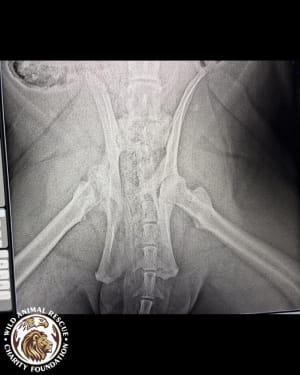

Тварині лише рік, але вона вже стала глибоким інвалідом. Тигриця не здатна самостійно підвестися і ледве пересувається, спираючись виключно на передні лапи. Після ретельного обстеження ветеринари були шоковані станом кісток молодого хижака.

• Двобічна дисплазія кульшових суглобів.

• Остеоартроз та патологічне ремоделювання головки стегнової кістки.

Лікарі утримуються від оптимістичних прогнозів. Процес лікування ускладнюється великою масою тіла хижака та сильною крихкістю кісток, які просто не витримують навантаження. Оскільки тигриця фізично не може довго лежати нерухомо, терапія стає справжнім викликом.

Наразі українські волонтери ведуть активні перемовини із закордонними експертами, щоб підібрати найменш болісний курс лікування. Проте дива не станеться: навіть за найуспішнішого сценарію деякі зміни у скелеті є незворотними. Тварина вже ніколи не стане повністю здоровою і до кінця свого життя потребуватиме спеціальних умов та постійної підтримки.